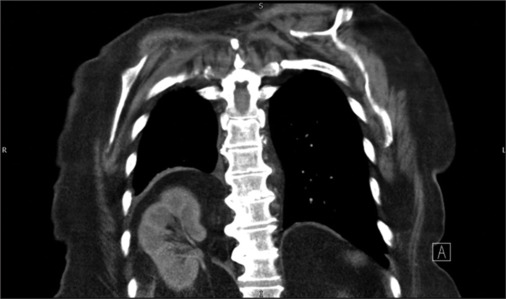

纵隔肿块:急诊诊断困境。

Mediastinal mass: Diagnostic dilemma on acute medical take.